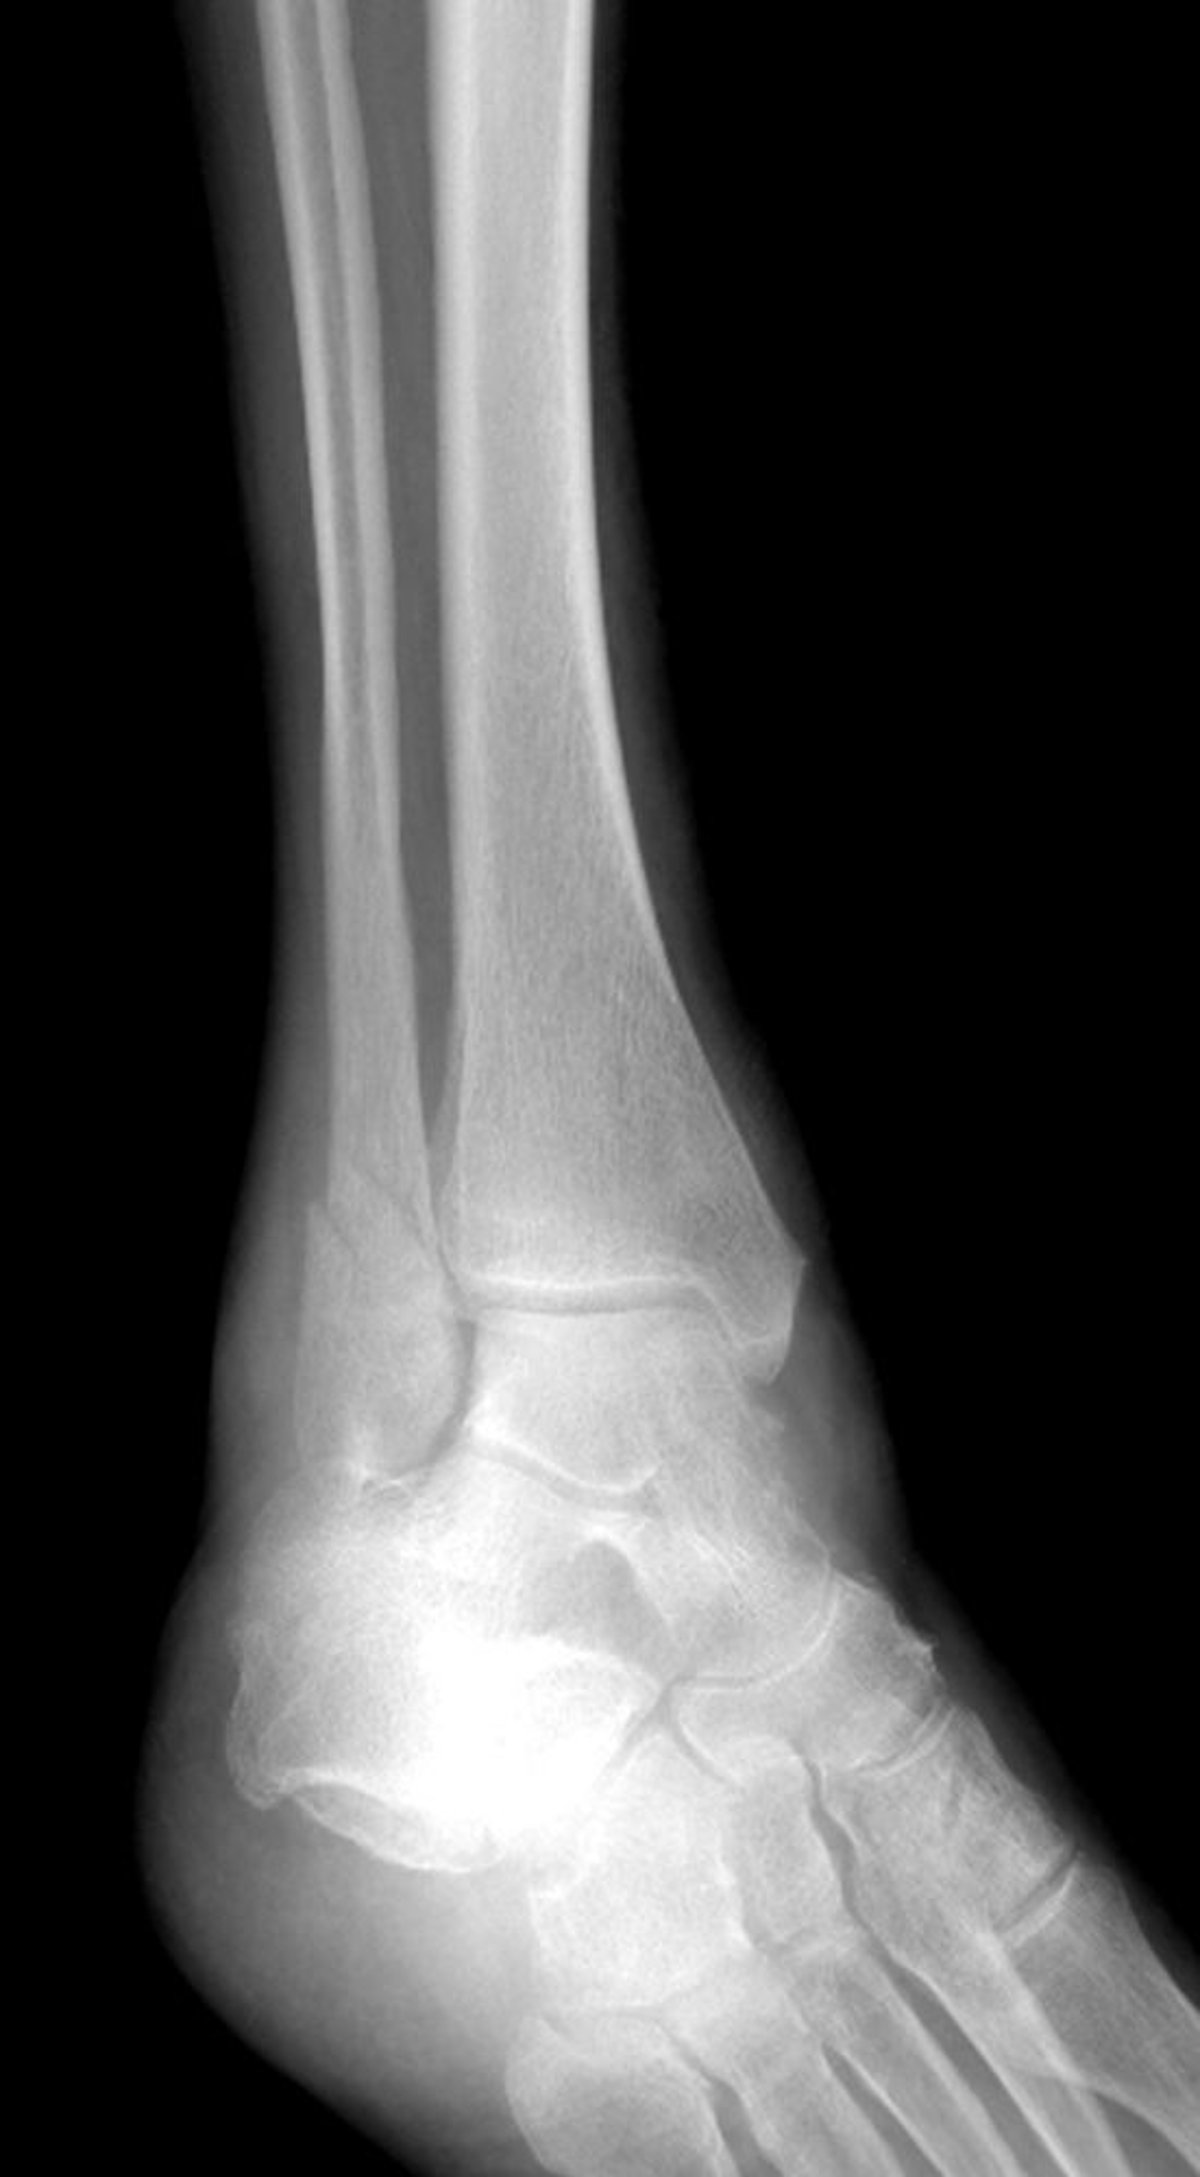

外果骨折

この足関節骨折は外果に及んでいるが,内果には及んでいない。